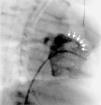

Case 3A 19-day-old baby boy was admitted to a Pediatric Intensive Care Unit following cardiorespiratory arrest of unknown cause. Cardiac catheterization to rule out anomalous coronary artery anatomy was performed and the right ventricular angiogram revealed a fistulous tract between the RV and the pulmonary artery (Figure 3).